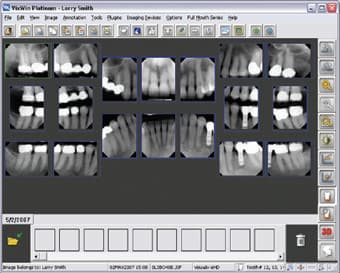

Digital Imaging—Life-Changing Technology

Digital imaging is part of efficient communication, and it adds to the “wow factor.” Patients may see their teeth in the mirror every day, but we must supply images that will let them learn about improving their dentition. For this, digital radiography has become the standard of care in diagnostics. This technology provides superior-quality images in a couple of seconds. It is an excellent diagnostic aid with which to compose a treatment plan. On the screen, we can enhance or zoom in, invert or emboss an image to communicate the possibilities in an unobtrusive way. Sometimes a patient may have a problem such as a fractured restoration that cannot

Digital Imaging – It’s a Win-Win for Everyone!

When patients are educated about the details of their dental health, they are more likely to understand the value of treatment. In my quest to improve my patients' dental experience, about two years ago, I began to explore the various options for digital radiography. At first, I was apprehensive about going digital and how this would affect workflow. After a short training period with my staff, I was happily convinced-digital-imaging advancements improve patient care. One very apparent positive aspect of digital imaging is connected with my imaging software-it both makes my job easier and involves the patients in their own treatment. This easy-to-use imaging software captures and mounts X-rays, offers